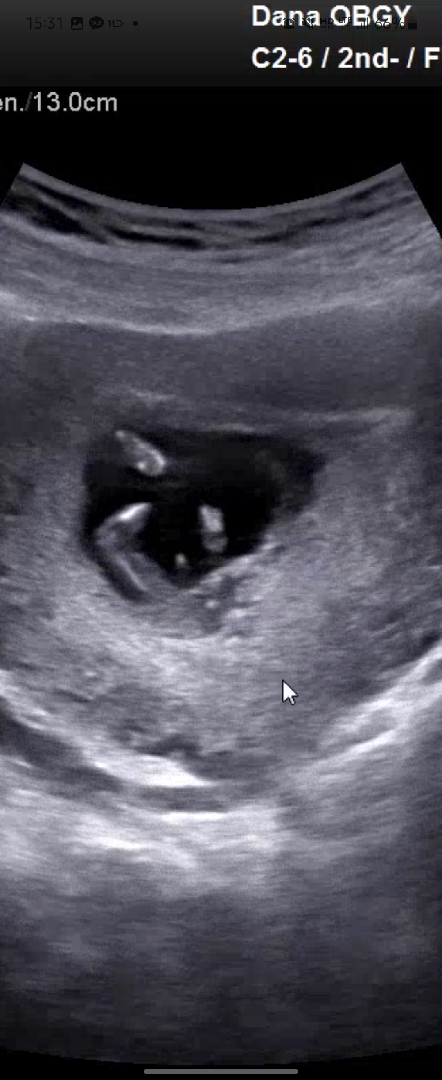

이거 혹시 고추인가요...?!

12주 2일차 입니다 !!!! 참견 마구마구 부탁드릴께요!!!

다른각도 입니다 !